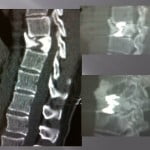

Vertebroplasty technique for vertebra-plana.

The position of the patient in hyperlodosis in order to reduce the fracture and increase the intra-somatic space is important. We systematically perform a extra-pedicular access or intercosto-vertebral access so that the trocar as more mobility in the vertebrae. The progression of the trocar is performed under scopic guidance, the penetration must be strictly intra-corporeal in the same axis as the fracture. A scanner control confirms the position in the fractured zone, the bevel of the trocar is oriented toward the important residual bone surface. We fill a first part of the vertebrae with a few drops of liquid cement to judge and anticipate the positioning and the frequent discal leaks. Under continual scopy, we visualize a linear diffusion intra-vertebral of the cement. Then we wait a few minutes to allow polymerization and get a high viscosity cement that we will push slowly in the cannula with a needle. The large viscosity at the end of the procedure is a key element to the correct filling of these fractures. The injection can be performed by filling the canulae and pushing the cement with the trocar. In case of a cement that is too liquid and a too large pressure applied at the point of intra-corporeal injection, the cement comes back up in the perforated needle to limit the risk of leaks at the epidural level. A thick and old cement diffuses close to the distal end of the trocar. Similarly the progressive retreat of the trocar by pushing to the needle the rest of the cement allows for perfect cementing in the rest of the way.

The subchondral space must be perfectly filled, the pressure in this space being smaller, the diffusion is easy. Also, a gain in height is frequently observed in this type of lesions. The post-operation precautions are the same as for osteoporotic fractures.